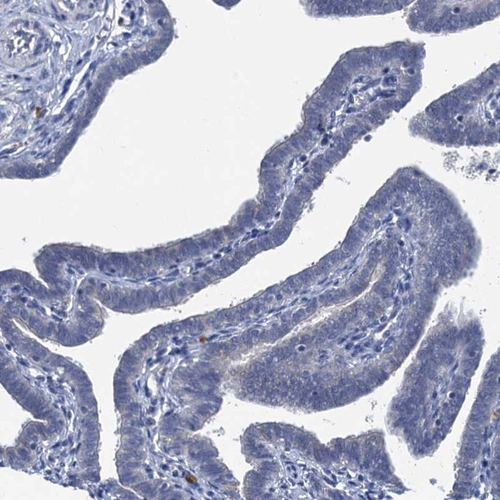

Immunohistochemical staining of human lung shows moderate cytoplasmic positivity in macrophages.